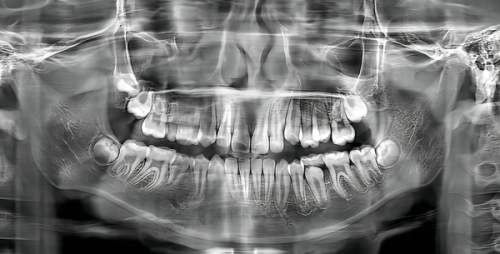

数字化种植牙:采用精良的数字化种植牙技术,利用三维影像技术对患者口腔进行精细扫描,并结合计算机辅助设计,为患者制定个性化的种植方案。这种技术能确保种植牙的精细度和美观度,让患者拥有自然、稳固的牙齿。

隐形矫正:提供隐形矫正服务,采用透明的矫正器,美观舒适且不易察觉。对于那些追求美观,不想因佩戴传统矫正器而影响形象的患者来说,是非常合适的选择。